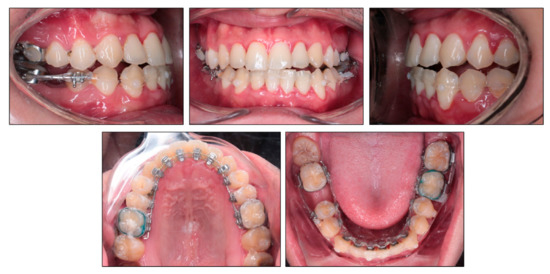

2.5. Treatment Progress